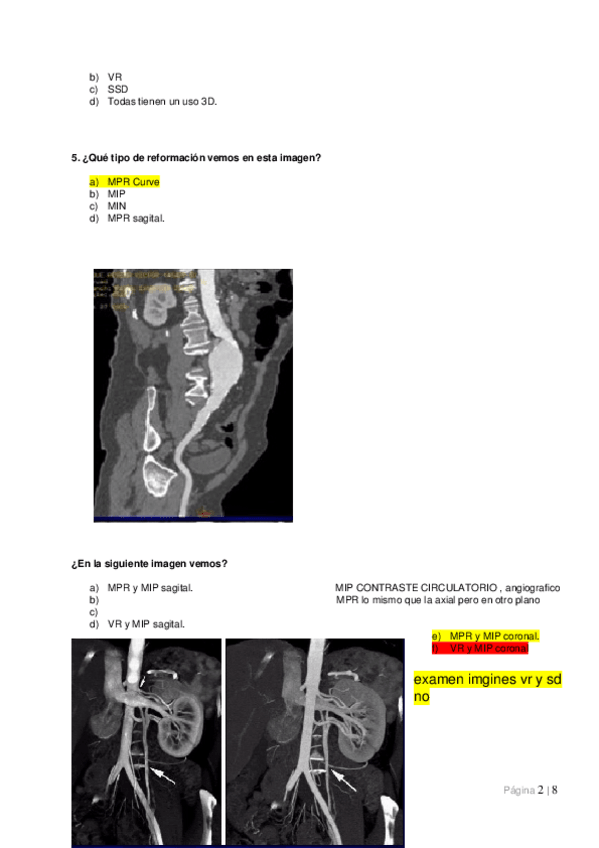

Unidades Hounsfield, ventanas, parámetros de calidad de la imagen, artefactos y reconstrucciones.

He publicado nuevos apuntes de Técnicas de Tomografía Computarizada y Ecografía: Tema-10.-Artefactos-y-postprocesado-de-la-imagen-en-TC.pdf

5 páginas